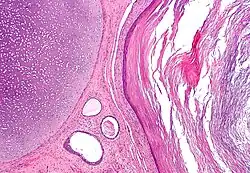

A mature teratoma is a grade 0 teratoma. They are highly variable in form and histology, and may be solid, cystic, or a combination of the two. A mature teratoma often contains several different types of tissue such as skin, muscle, and bone. Skin may surround a cyst and grow abundant hair (see dermoid cyst). Mature teratomas generally are benign, with 0.17-2% of mature cystic teratomas becoming malignant.[16]

Teratomas are also classified by their content; a solid teratoma contains only tissues (perhaps including more complex structures); a cystic teratoma contains only pockets of fluid or semifluid such as cerebrospinal fluid, sebum, or fat; a mixed teratoma contains both solid and cystic parts. Cystic teratomas usually are grade 0 and, conversely, grade 0 teratomas usually are cystic.